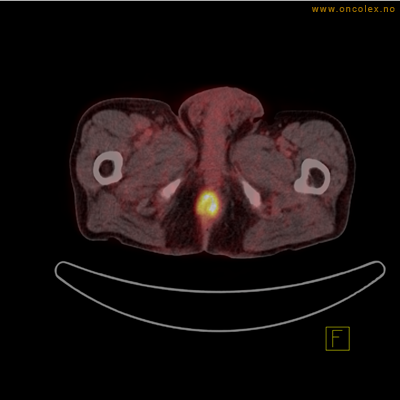

Eksempler på funn

Vev som tar opp mer radioaktivt stoff, synes som hvite områder som lyser opp mer i forhold til annet vev som tar opp mindre sukker.